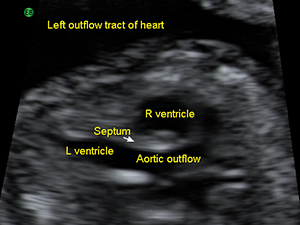

胎兒心臟主動脈外流道平面圖